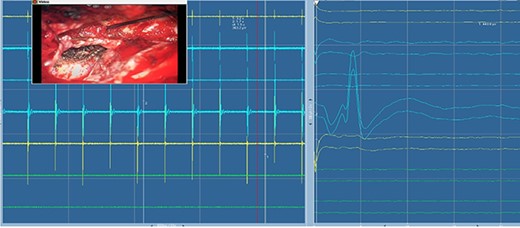

Electromyography of trigeminal nerve (motor). Trigger EMG of the motor branches of the trigeminal nerve with positive motor responses (mentalis muscle EMG). Nearby cranial nerves were additionally monitored including the facial nerve CN VII (orbicularis oculi, orbicularis oris and mentalis muscle) and abducens nerve CN IV (lateral rectus muscle).

Direct nerve stimulation of the sensory V2. Direct nerve stimulation of the sensory branch V2 at the foramen ovale demonstrating cortical SSEPs recorded from scalp electrodes (montages C4’-Cz’, C4’-Fz, C4’-C3’) accordingly to the international 10–20 EEG system. Average latency: 5.4 ms, amplitude: 12.5 μV.

Trigeminal V2 SSEP recordings. Trigeminal V2 SSEPs were continuously recorded on the scalp using the montage C4’-Fz. Average latency: 5.4 ms, amplitude: 13 μV.

Blink reflex. Blink reflex from left side stimulation of the supraorbital branch of the trigeminal nerve was observed with EMG activity from left orbicularis oculi muscle. Both early response (R1) and late reflex activity (R2) were recorded throughout the surgical procedure.